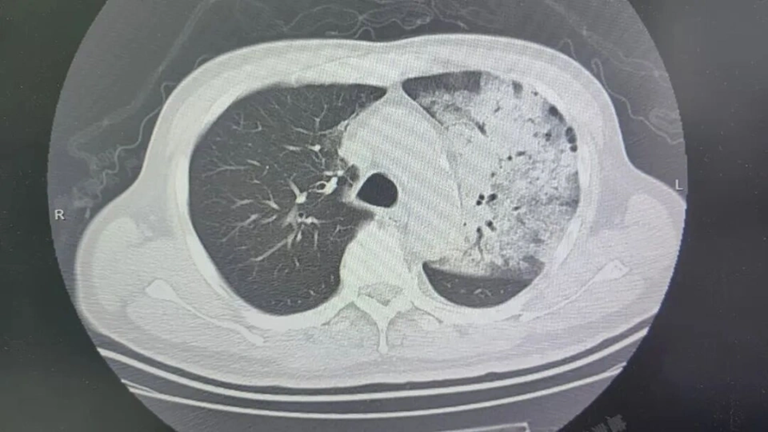

Sau khoảng một tuần điều trị tại bệnh viện địa phương, bệnh tình của ông đột ngột xấu đi. Bệnh nhân bắt đầu khó thở, rối loạn ý thức. K ết quả chụp CT cho thấy 2 phổi bị nhiễm trùng nặng, gần như “trắng xóa” . Dù đã được hỗ trợ thở máy nhưng tình trạng oxy máu vẫn không cải thiện.

Người đàn ông sốt 40 độ C, phổi gần như "trắng xóa", chỉ vài ngày đã suy đa tạng: Thủ phạm liên quan đến thói quen nhiều gia đình vẫn mắc- Ảnh 1.